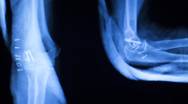

Risikoen for skadevirkninger efter røntgenbilleder er meget lille. Moderne røntgenapparatur er designet til at tage billeder af meget høj kvalitet ved brug af meget lave stråledoser.

Størrelsen af stråledosis afhænger af hvilken type røntgenundersøgelse, der skal foretages. Fx giver CT-scanning mere stråling end almindelig konventionel røntgenoptagelse. Stråledosis er et mål for den mængde energi, som kroppen absorberer ved en undersøgelse. Dosis måles i Sievert (Sv), som er en stor enhed. Derfor angives stråledosen ved røntgenundersøgelserne normalt i millisievert (mSv). 1 Sv = 1.000 mSv.

En mammografi undersøgelse giver eksempelvis 0,5 mSv.

En CT-scanning af hele kroppen giver 10 mSv.

Røntgen af brystkasse giver 0,1 mSv

Til sammenligning får en dansker i gennemsnit en naturlig stråledosis på ca. 3 mSv om året. Denne stråling stammer fra Radon, jordskorpen, fødevarer samt kosmisk stråling.